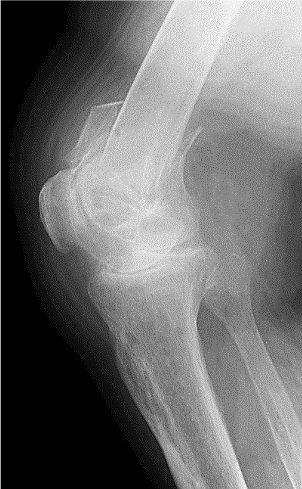

76 yo

Changing the bulb in the corridor

Felt from the ladder directly onto the right knee

Pain/ swelling/ 0 ROM/ unable to WB

What is this ?

What can be an issue with this ?

Femoral Supracondylar fracture